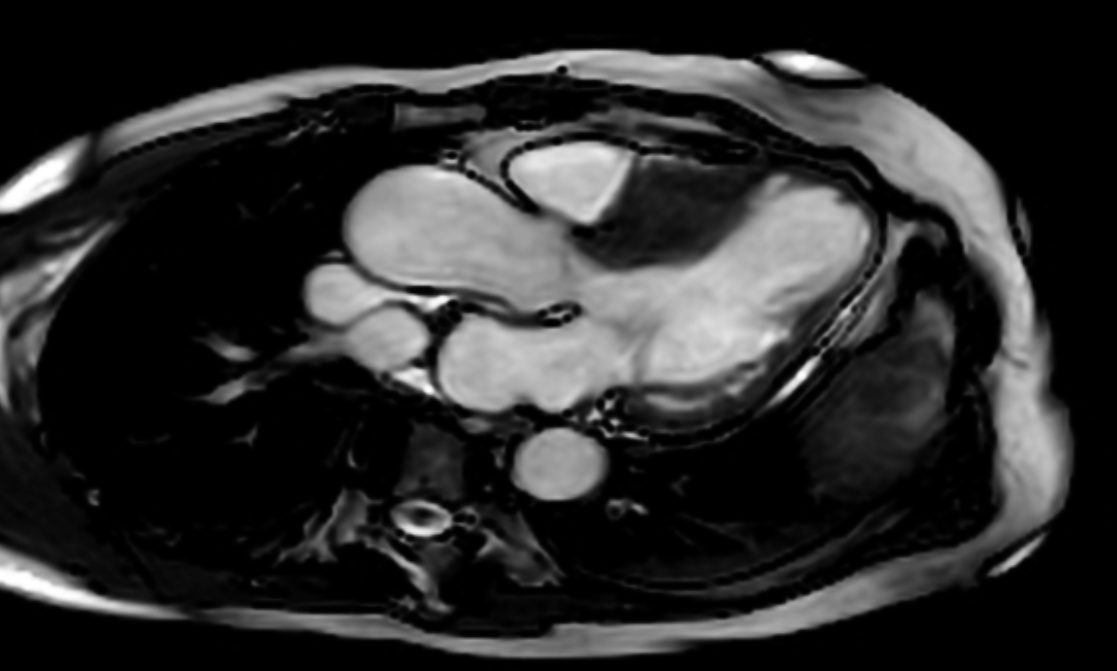

Clinical Case [Uncaptioned image] [Uncaptioned image]

Image Findings: The patient underwent contrast-enhanced computed tomography which showed features of a congested liver with flip-flop pattern of enhancement. Hepatic veins show hypoattenuation on delayed phase. An accessory hepatic vein is also noted in segment VI. A diagnosis of Budd Chiari syndrome (BCS) was made on the basis of the clinical and imaging features. The patient was referred to the interventional radiology team for an endovascular rescue. On conventional venogram, the diagnosis of BCS was confirmed as the hepatic veins were thrombosed. An accessory segment VI hepatic vein was noted draining into the IVC…

Title: Accessory right inferior hepatic vein [Uncaptioned image] [Uncaptioned image]

Discussion:Marked dilatation of the pulmonary trunk (6.7 cm) with the right (5.4 cm) and left (4 cm) main branches. Lung window shows mild bilateral diffuse faint groundglass centrilobular lung nodules that may reflect an underlying infection. Scans through the upper abdomen revealed average size cirrhotic liver and reflux of contrast into the IVC and hepatic veins with Incidental opacification of accessory right inferior hepatic vein…